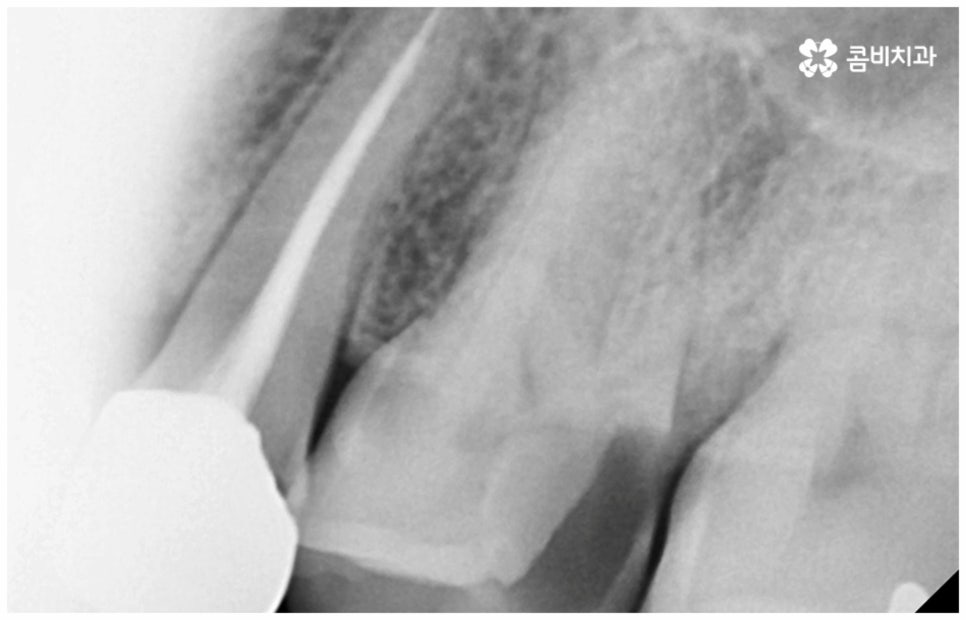

여기서 어금니신경치료 란 법랑질과 상아질을 지나 치아 안쪽 깊은 곳의 치수 조직까지 감염이 되었을 때 손상 부위를 모두 제거하고 치근관을 소독, 밀폐하는 치료를 의미하고 있는데요. 사람의 치신경은 아주 얇고 치근관의 모양과 개수는 모두 다 다른데 만약 끝이 구부러져 있거나 미세 부근관이 여러 갈래로 많이 퍼져 있는 경우, 신경관이 막힌 경우라면 신경을 제거할 때 난이도가 올라가므로 더욱 주의깊게 치료할 필요가 있어요.

감염 조직을 완전히 제거하지 않으면 통증이 지속될 수 있고 재발 가능성 또한 높아지므로 어금니신경치료 시 담당의 선생님의 높은 숙련도 및 세심한 기술력이 요구되고 있는데요. 혹시 모를 부작용을 방지하기 위해 3D CT 와 같은 정밀 진단 기계를 갖추고 신경관의 위치와 모양, 환자분들의 골조직 및 치아까지의 거리 등을 꼼꼼하게 파악하여 치료 계획을 세운 후 손상 부위를 세심하게 제거한다면 고난도의 경우라도 보다 안전하게 진행할 수 있어요.